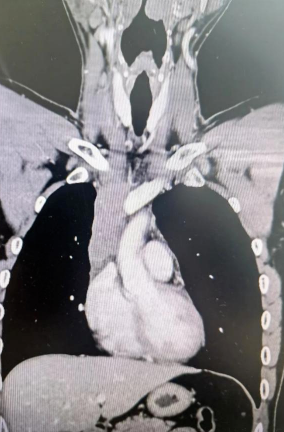

經檢查發(fā)現患者前上縱隔腫瘤已經完全侵犯了我們人體最主要的大靜脈之一——上腔靜脈,導致上腔靜脈回流嚴重受阻并導致由上腔靜脈起至左側無名靜脈、右側鎖骨下靜脈、右側頸內靜脈等多根自上往下回流的靜脈阻塞,從而形成了廣泛的栓子,牢牢堵住了要流回心臟的血流,只能靠別的一些側支循環(huán)超負荷的工作,這也就是為什么孫先生脖子甚至是頭都明顯腫起來的原因。

4月30日,麻醉完成后,縱劈胸骨顯露右上縱隔腫瘤,發(fā)現腫瘤侵入上腔靜脈起始部,右鎖骨下靜脈及右頸內靜脈血栓形成并向遠端延伸。劉志主任團隊將切口向右頸部延長,顯露右側頸內靜脈至下頜角水平。張金洲副院長團隊經股動靜脈和左無名靜脈建立體外循環(huán)。在阻斷左無名靜脈遠端后,李文海副院長團隊完整切除縱隔腫瘤及部分上腔靜脈、左無名靜脈、右鎖骨下靜脈和右頸內靜脈切除。張金洲副院長團隊實施了無名靜脈近端、右鎖骨下靜脈和右頸內靜脈內血栓取出術,并完成了左無名靜脈、右頸內靜脈和右鎖骨下靜脈的人工血管置換手術。歷時6小時,三個外科團隊在麻醉科柴偉主任團隊、體外循環(huán)團隊以及食管超聲和手術室協(xié)作下,手術獲得成功。

術后患者經過心外監(jiān)護室和胸外監(jiān)護室的接力治療,目前患者恢復順利,顏面部腫消失。復查增強CT三條人工血管通暢。